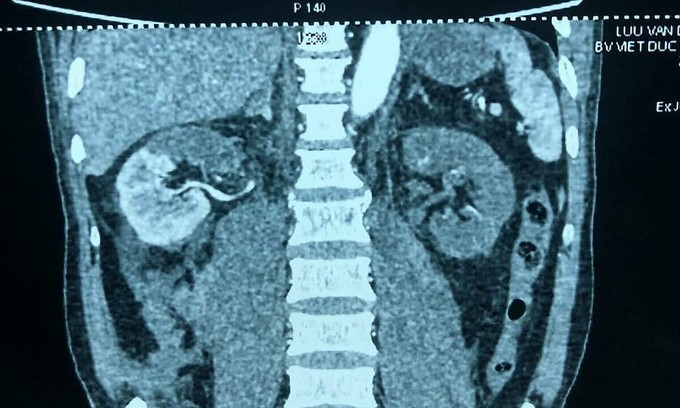

Phim X-quang trước mổ cho thấy thận phải mất 1/2 chức năng, thận trái mất hoàn toàn. - Ảnh: Vnexpress

Theo thông tin đăng tải trên Vnexpress, trước đó bệnh nhân bị tai nạn giao thông, bác sĩ ở Bệnh viện Hải Dương chẩn đoán chấn thương cột sống, chuyển tới Bệnh viện Việt Đức. Kết quả chụp chiếu cho thấy thận bên phải của bệnh nhân bị mất một nửa chức năng, thận bên trái thiếu máu, mất chức năng hoàn toàn. Chức năng thận giảm, có biểu hiện suy thận.